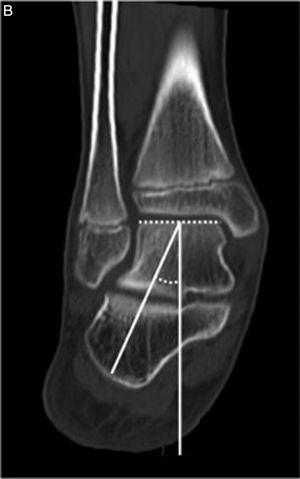

Evaluación de las imágenesTodas las imágenes fueron realizadas en la misma institución, con la misma técnica. El estudio se llevó a cabo con un tomógrafo Siemens Somatom Sensation con apoyo en soporte. El análisis y almacenamiento de las imágenes se realizaron con un software de imágenes Kodak Carestream PACS versión 10.2. Tres profesionales evaluaron las imágenes con el sistema PACS Carestream, con las herramientas de medición pertinentes. Para determinar los ángulos, se empleó el corte en el plano sagital del pie que permite observar la base del segundo metatarsiano, trazando una línea que pase por el 50% de la articulación subastragalina posterior. Luego se trasladó ese corte al plano coronal (fig. 1A). En el plano coronal se midió el AAC que es una adaptación del ángulo descripto por Wilde et al.8 y representa la alineación en conjunto del retropié. El mismo se forma entre una la línea perpendicular al domo astragalino y otra perpendicular al borde inferior del calcáneo (fig. 1B).

A) Corte sagital del pie, que toma la base del segundo metatarsiano. En este corte se traza una línea que atraviese el centro de la articulación subastragalina posterior. Ese corte se trasladó al plano coronal para realizar las mediciones. B) Ángulo astrágalo-calcáneo formado entre una línea perpendicular al domo astragalino y otra perpendicular al borde inferior del calcáneo.